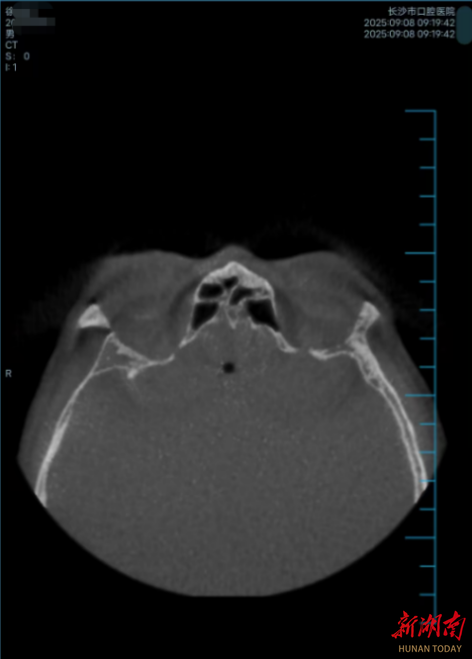

上线云影像系统

作为年度智慧医疗重点工程,云影像系统于2025年1月1日成功上线并稳定运行。截至年底,已生成云影像数据近299347例。患者可通过手机随时调阅、分享自己的影像检查结果,实现了“让数据多跑路,让患者少跑腿”,标志着我院向“无胶片化”智慧医院迈出关键一步。